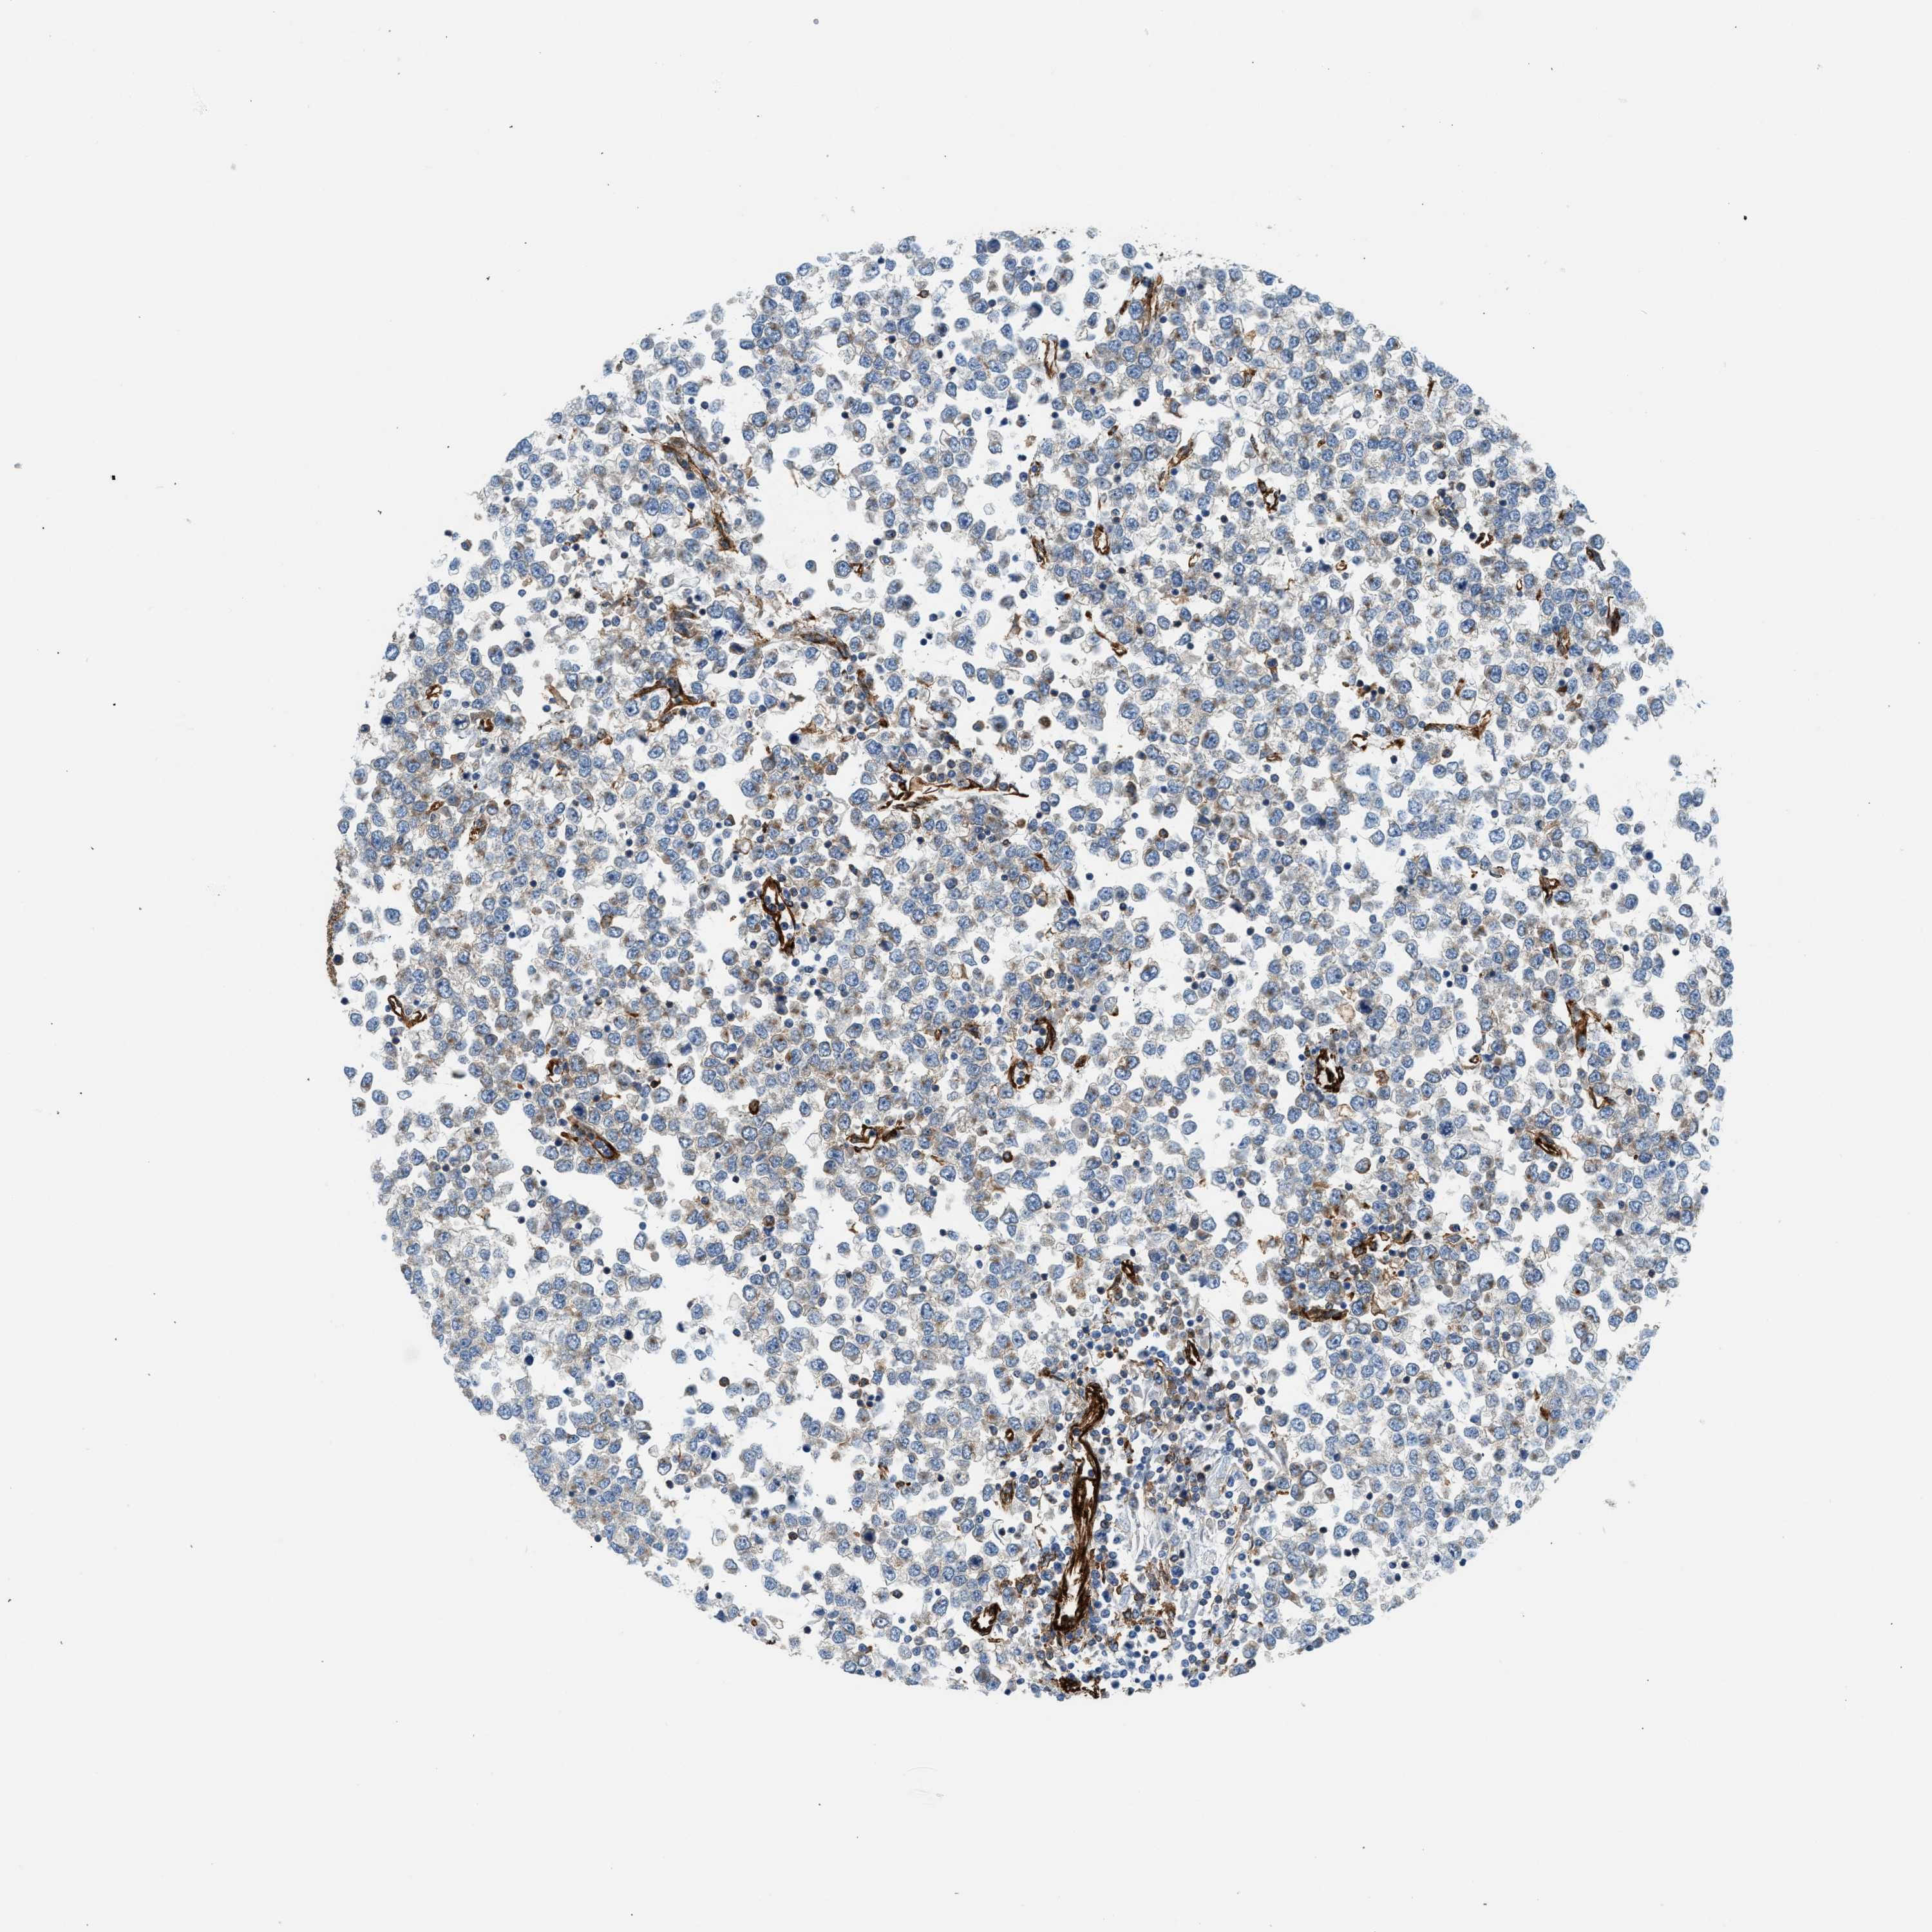

TESTIS CANCER - Protein expressioni

A mouse-over function shows sample information and annotation data. Click on an image to view it in a full screen mode. Samples can be filtered based on level of antibody staining by selecting one or several of the following categories: high, medium, low and not detected. The assay and annotation is described here.

Note that samples used for immunohistochemistry by the Human Protein Atlas do not correspond to samples in the TCGA dataset.

Antibody stainingi

Antibody staining in the annotated cell types in the current human tissue is reported as not detected, low, medium, or high, based on conventional immunohistochemistry profiling in selected tissues. This score is based on the combination of the staining intensity and fraction of stained cells.

Each image is clickable and will lead to virtual microscopy that enables deeper exploration of all samples and also displays staining intensity scores, fraction scores and subcellular localization as well as patient and tissue information for each sample.

Antibody HPA013606

Carcinoma, Embryonal, NOS

Seminoma, NOS